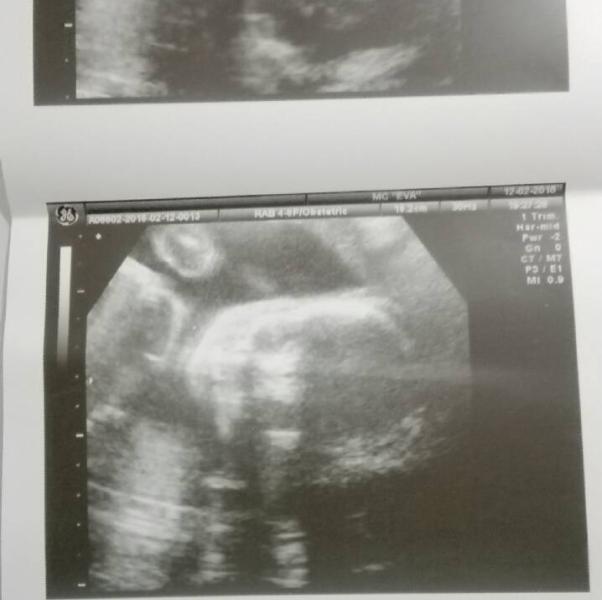

#длиннопост о нашем походе на 3д УЗИ) ходили мы в Еву к Минайчевой. Все понравилось, но 3д мы так и не получили,но об этом позже) Так вот, там висит монитор перед носом мамочки и второй монитор для доктора и мужа)Включает она оборудование и на мониторе появляется ОНО😂И следом комментарий врача "У вас мальчик,вы знаете?". Нам до этого точно никто не говорил, но здесь все и так видно было, мужик💪По показаниям все хорошо, за 4 недели от планового УЗИ малыш вырос в 2 раза😱И весим мы 610 грамм. Срок ...